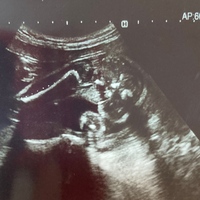

妊娠25週2日 25w2d の超音波 エコー 写真

7ヶ月検診 25週のエコー写真 初めての妊娠と出産の記録

妊娠25週目 25w0d 6d のエコー写真とエピソード 妊娠7ヶ月 Cozre コズレ 子育てマガジン

医師監修 妊娠25週のエコー写真 髪は生えていても顔はまだしわっぽい マイナビ子育て